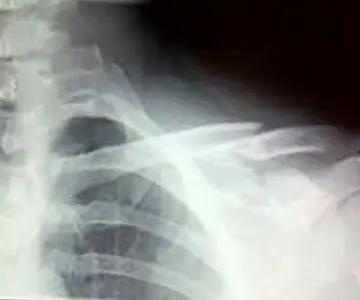

“Zoncolan Alpi Friuliani... epic crash fractures my clavical + 2 ribs but wont shatter my Kona dreams” ha scritto in bacheca il noto personaggio televisivo poco dopo le 19. E un’ora più tardi i commenti con gli auguri per una pronta guarigione erano già centinaia e centinaia, pubblicati subito sotto la foto della radiografia dell'osso postata sempre dal noto chef.

«Un grande grazie ai Dottori dell'ospedale di Udine!» ha anche aggiunto Bastianich che è stato curato nel reparto di Ortopedia del Santa Maria della Misericordia.